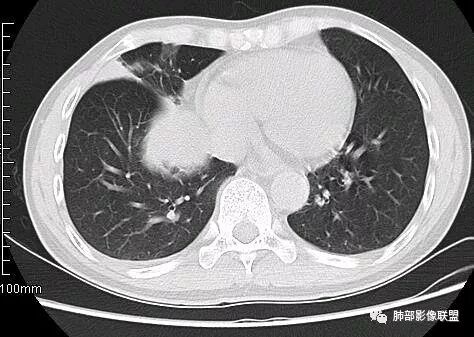

南边:从叶裂的变形,下朝上,越来越朝前扭曲,提示叶裂局部有朝前上推移的趋势

南边:下叶的支气管受压后移、变形

南边:病灶边界清,提示侵袭性弱,膨胀生长为主;这时候我们提示病灶不应该是支气管关系密切,提示间叶来源或胸膜来源

深分叶,警惕恶性